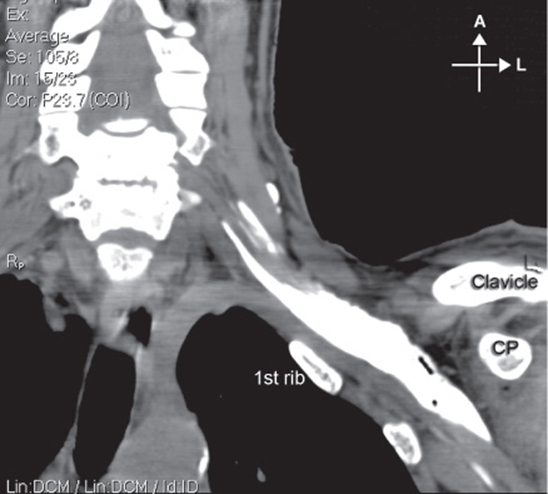

An X-ray film demonstrates the relevant anatomy (Figure 14-8):

FIGURE 14-8. Osseous prominences of significance to infraclavicular brachial plexus block and relationship to the chest wall. Shown also is distribution of the local anesthetic underneath the clavicle after injection of the contrast-containing local anesthetic.

1. Coracoid process

2. Clavicle

3. Humerus

4. Scapula

5. Rib cage.